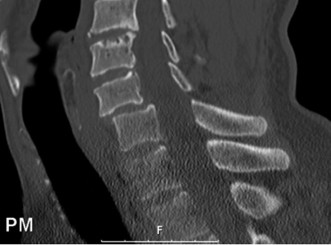

The correct answer is (A). As the case scenario strongly suggests an injury to the spine at the thoracolumbar junction, a CT scan of both the thoracic and lumbar regions is indicated. An MRI should not be the first imaging study obtained. Standing films should not be obtained in a trauma patient with a potentially unstable spine injury. A CT myelogram would only be obtained if an MRI was indicated but the patient had a contraindication to an MRI. Images of the above patient are shown inFigures 1–25 and 1–26. This injury is best characterized as which of the following? 1. Compression fracture

Figure 1–25

Figure 1–26

The correct answer is (B). The images demonstrate an L1 vertebral body fracture with a small degree of kyphosis. There is comminution of the vertebral body with a posterior vertebral body fragment that is slightly retropulsed into the spinal canal. This separate posterior vertebral body fragment (which is noncontiguous with the pedicles) is the hallmark of a burst fracture. Compression fractures do not have any posterior vertebral body involvement. A Chance fracture, also known as a seat belt fracture or flexion–distraction injury, will exhibit distraction of the posterior elements through bone, bone-ligament, or purely ligament structures, with an axis of rotation somewhere within the anterior vertebral body or anterior to the vertebral body. A fracture dislocation exhibits translational deformities between the injured levels. While there appears to be a translational deformity on the sagittal CT, the vertebral bodies of the uninjured levels above and below are actually well aligned.